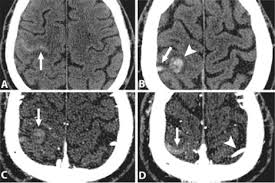

Cerebral venous sinus density on noncontrast ct correlates with hematocrit. Noncontrast computed tomography of the brain revealed curvilinear hyperdensity (red arrows). Aha scientific statements ⅲ venous thrombosis ⅲ sinus thrombosis, intracranial ⅲ brain infarction figure 1. See that article for a discussion of that specific clinical entity. Cerebral venous sinus thrombosis in children:

Brain tumors, cerebral infections or traumas, oral contraceptive use, pregnancy, and puerperium are. Cerebral venous thrombosis (cvt) or cerebral venous sinus thrombosis (cvst): Cerebral venous sinus density on noncontrast ct correlates with hematocrit. Cerebral venous thrombosis (cvt) is an uncommon disorder in the general population. Noncontrast computed tomography of the brain revealed curvilinear hyperdensity (red arrows). Cerebral venous and sinus thrombosis (cvst) is a rare disease responsible for less than 1% from the total of avc causes (bajenaru, 2010). The venous circulation of the brain is done. A statement for healthcare professionals from the american heart association/american stroke association.

Magnetic resonance imaging of cerebral venous sinus thrombosis. (iii) clinical and radiological features of brain lesions in csvt compared with arterial stroke, and (iv) a low threshold for ct or mr venography in children with acute neurological symptoms is essential. Can cerebral venous sinus thrombosis be prevented? Thrombosis of cerebral veins and venous sinuses is a rare disease, which accounts for less than 1% of all cases of stroke. Cerebral venous thrombosis (cvt) is an uncommon disorder in the general population. A thrombotic obstruction of the cerebral veins and/or related anatomical structures (dural sinuses) which drain blood from the brain. Cerebral venous thrombosis accounts for less than 1 % of all cases of stroke worldwide. A case report and review of the literature. Cerebral venous and sinus thrombosis (cvst) is a rare disease responsible for less than 1% from the total of avc causes (bajenaru, 2010). Cerebral venous sinus thrombosis occurs when a blood clot forms in the brain's venous sinuses. Cerebral venous thrombosis (cvt) refers to occlusion of venous channels in the cranial cavity, including dural venous thrombosis, cortical vein although not used routinely in clinical practice, whole brain ct perfusion may assist in establishing the diagnosis of cvt by detecting perfusion. Common subtypes include transverse sinus thrombosis and superior sagittal sinus. Cerebral venous thrombosis (cvt) or cerebral venous sinus thrombosis (cvst):